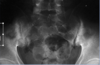

What can you see in imaging of sacroiliac joint in ankylosing spondylitis

Irregular SI joint, increased whitening on either side